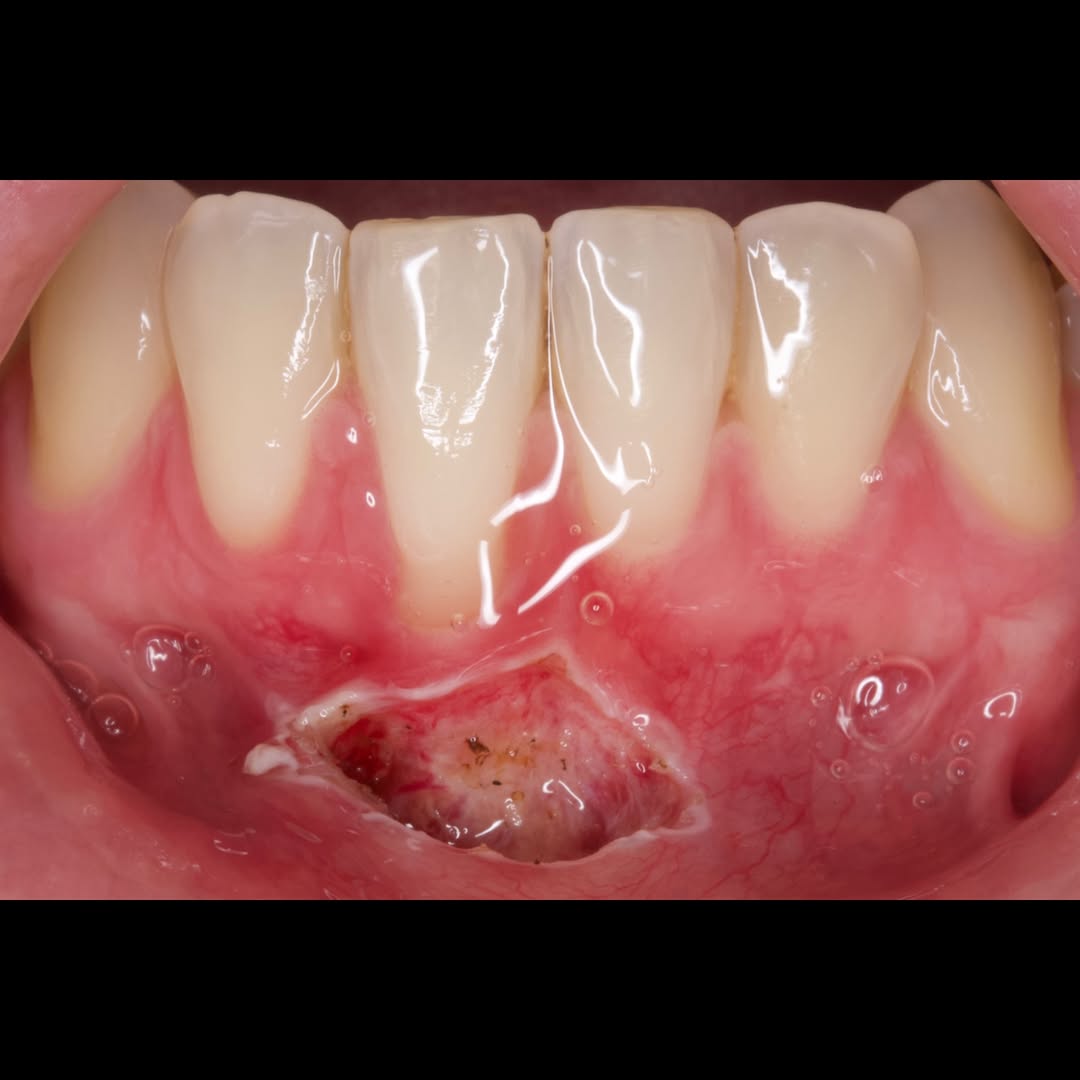

Durante una mañana, asistirás a una Cirugía Mucogingival de recubrimiento radicular de recesiones múltiples en IV y V sextante (36 a 43).

Gracias al uso del microscopio y a la proyección en tiempo real en pantalla, verás exactamente lo mismo que veo yo durante la cirugía, sin tener que estar

Durante una mañana, asistirás a una Cirugía Mucogingival de recubrimiento radicular de una recesión unitaria en 31 con frenillo asociado. Gracias al uso del microscopio y a la proyección en tiempo real en pantalla, verás exactamente lo mismo que veo yo durante la cirugía, sin tener que estar